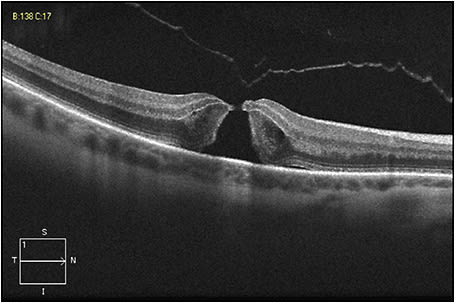

Figure 1 shows an eye in this series, with FTMH measuring 216 µm and concurrent focal VMT; this patient’s best-corrected Snellen VA was 20/70. Figure 2 shows VMT release following intravitreal ocriplasmin, with a decrease in VA to 20/200 at one week following injection. Figure 3 demonstrates an increase in FTMH size (now measuring 264 µm) at 12 days following injection.

Figure 3. An increase in FTMH size (now measuring 264 µm) occurred at 12 days following injection.